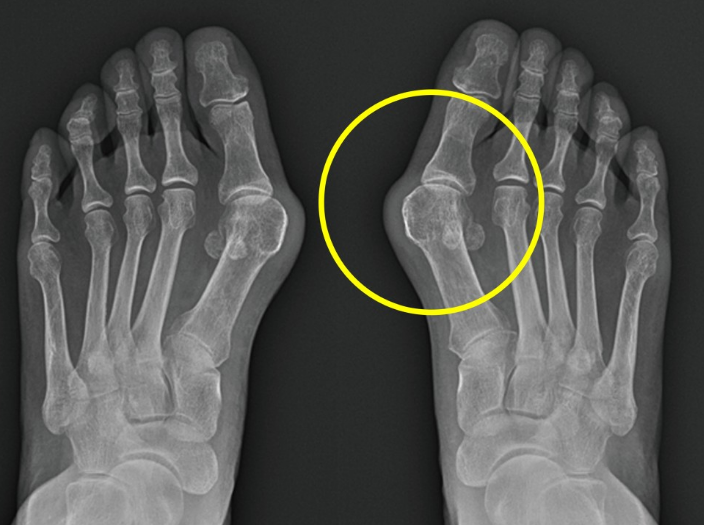

우리가 흔히 알고 있는 무지외반증 때문입니다. 사전적 의미는 엄지발가락이 안쪽으로 튀어나오는 변형이 생겼다는 말입니다. 하지만 실제로 따지고 보면 발가락과 발등을 연결하는 중족골이라는 뼈가 안쪽으로 벌어지면서 회전 변형이 같이 일어나는 질환입니다. 처음에는 증상이 없다가도 점차 진행하게 되면 발가락 안쪽이 점차 튀어나와 일반적인 신발을 신기가 불편한 증상이 생깁니다.

보행 시 첫번째 중족골이 힘을 잘 받쳐줘야 하는데 무지외반이 진행되면 다른 발가락의 중족골이 힘을 받으며 발바닥 쪽의 통증이 생기는 전이성 중족골통이 발생하기도합니다. 또한 심한 변형이 지속되면 발가락을 움직여주는 힘줄이 제 역할을 하지 못해 걷기 불편하기도 하며, 엄지발가락이 두번째 발가락을 밀면서 두번째 발가락까지 점차 변형이 진행되고 엄지발가락이 검지발가락에 올라타는 변형이 발생하기도합니다.